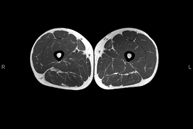

- Thigh MRI

Ideal examination for studying injuries to the hamstrings and quadriceps, which are frequently injured in athletes. It also allows for a good assessment of tendons and peripheral nerves. It lasts approximately 20 minutes. It is a radiation-free procedure.

- Knee MRI

Examination to study joint injuries, such as meniscal tears and cruciate ligament tears (only detectable through this test), chondropathy or cartilage wear, and a multitude of other disorders resulting from sports activities and degenerative changes (osteoarthritis). It lasts approximately 18 minutes. It is a radiation-free procedure.